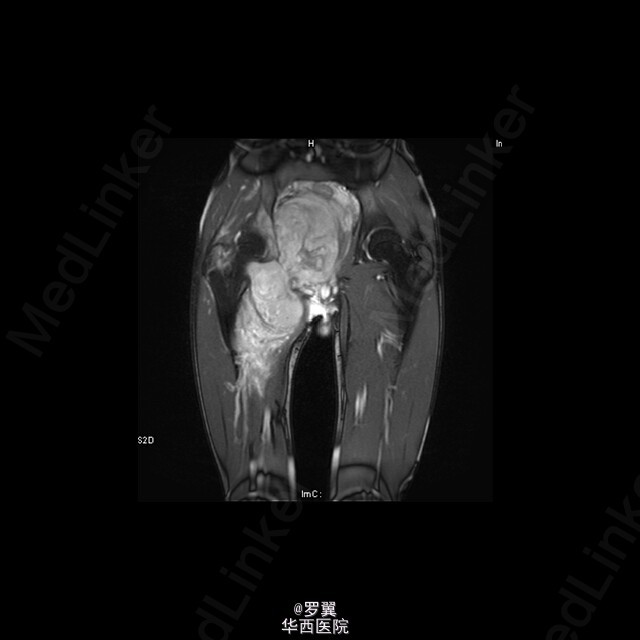

患者男,21岁,因“ 右髋疼痛7月伴右腹股沟包块2月”入院。查体:视:右腹股沟区可见一大小约15cmx10cm包块,未见浅表静脉怒张,无红肿及渗出,皮肤无破溃。触:质硬,边界不清,皮温稍高,局部深压痛。在右大腿根部前正中可扪及股动脉搏动。右侧鞍区感觉明显减退,右大腿上段内侧浅感觉减退。.肛门括约肌肌力Ⅲ级。动量:右髋伸90°,伸-10°。做伸直动作时患者包块区域疼痛加重。复查ct:盆腔巨大肿瘤,骨质破坏,考虑恶性肿瘤可能性大,核磁共振:考虑盆腔恶性肿瘤。入院后,完善相关辅助检查及术前准备,并采用阿霉素化疗方案化疗后,后在全麻下行腹主动脉球囊阻断下右侧骨盆肿瘤切除、腹股沟淋巴结清扫、人工组配式半骨盆置换术。术后1周即能拄拐下地,右髋能屈曲50°,右膝能屈曲65°。现出院。